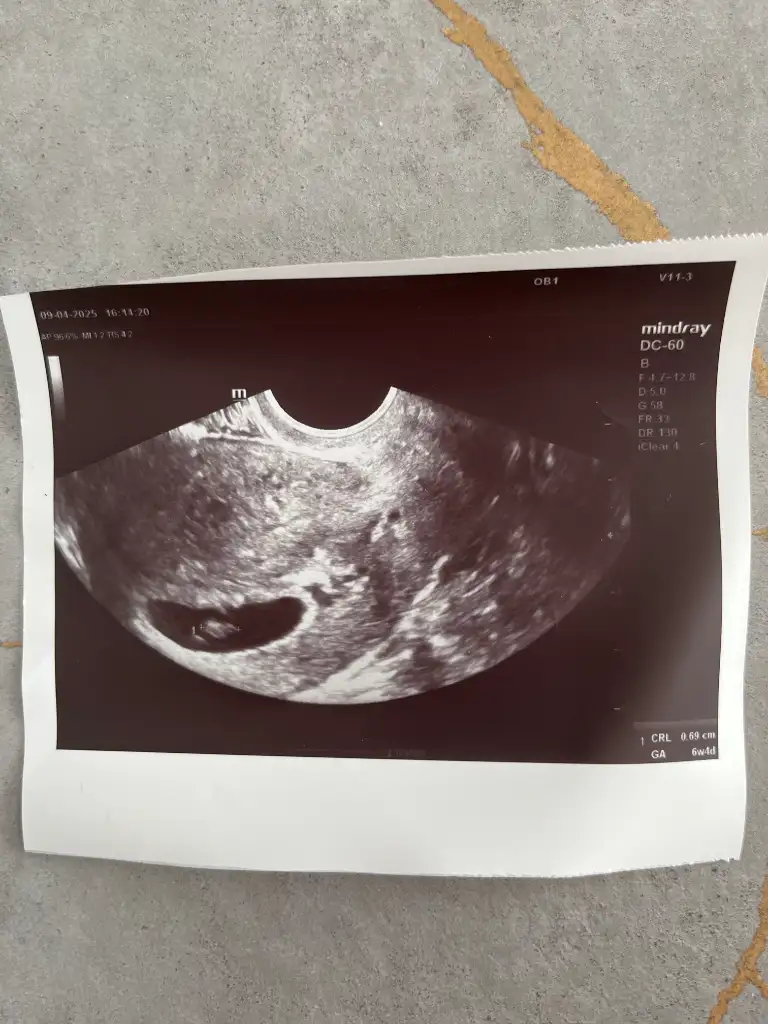

Gittim kızlar doktora devlet hastanesine karından baktı cihaz çok iyi değil bir de Vajinal ultrasonla bakalım dedi bebek dün karından 6,6 mm olarak ölçülmüştü bugün 6,9 mm olarak ölçüldü Vajinal olarak . Doktor bizim sınırınız 7 mmdir ondan sonra net bir kalp atışı bekleriz aslında bu hafta da duyan da var duymayan da endişe edilecek birşey yok pazartesi salıya kadar bekliceksin başka şansın yok dedi. Büyümüş mü kalbi atıyor mu bakarız dedi . İlginç bir şekilde dünden beri mide bulantılarım ve kusmalarım arttı kafamı kaldıramıyorum yani. İnşallah bir mucize olur beklemedeyim şimdilik . Kanmam ağrım yok çok şükür. Dualarınızı eksik etmeyin nolur 🙏

ne kadar teşekkür etsem az size 🥹 İnşallah daha güzel haberlerle gelirim haftaya . Bir tık inancım umudum yükseldi bu doktor sayesinde . Kadın kendi de dedi daha önce hiç duymadığın kalp atışına durmuş diyemezsin . Belki daha atmaya başlamadı neden bu kadar kürtaj yanlısı bu doktorlar dedi . Allah var ilgilendi karından baktı vajinal baktı . İyi bir insanmış olumsuz konuşup seni üzmem bana fayda sağlamaz ama sana zararı dokunur kesin bir durum olmadan kötüye yormak hastaya haksızlık dedi . Şaşırdım özeldeki bu kadar insaflı değildi . Kesen güzel dedi hatta resmini tekrar verdi atayım size de .

Evet kesen de güzel duruyor iyiki gütmişsin bu doktora da bak. Bazıları için hemen kürtaj demek ne kadar kolay geliyor. Bebeğin de büyümüş mü sanki biraz 6,6 dan 6,9 a çıkmış.